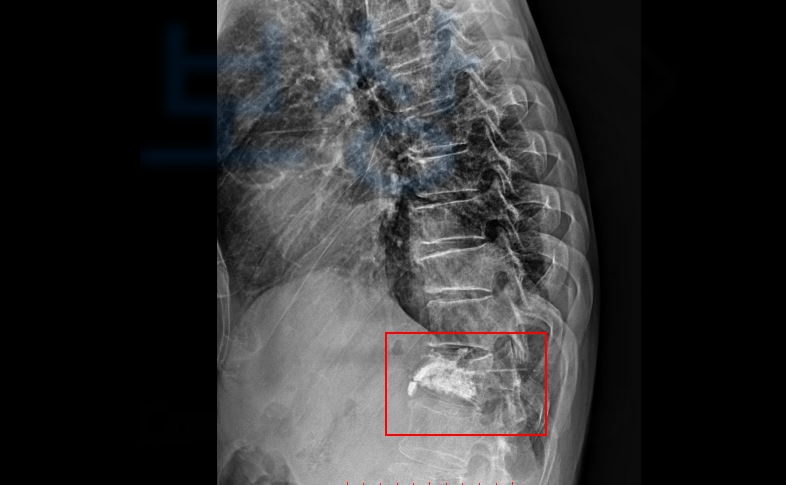

산에서 벌목 일을 하다 나무에 허리를 맞아 넘어지신 권@@님… 급히 병원으로 내원하여 정밀검사를 받아보니.. 흉추12번 골절 S22090

엑스레이 권@@님 척추체의 압박률을 보던 주치의는 척추성형술 즉 골시멘트 술을 권하였고